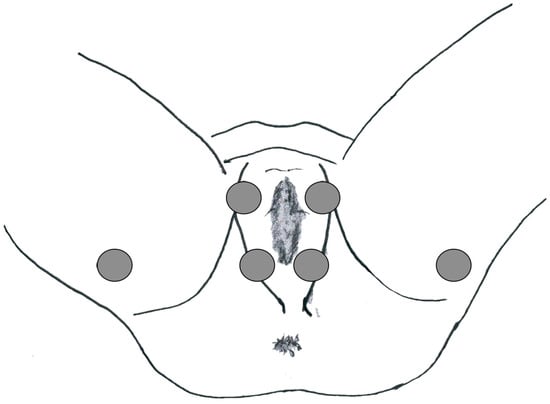

2. Materials and Methods